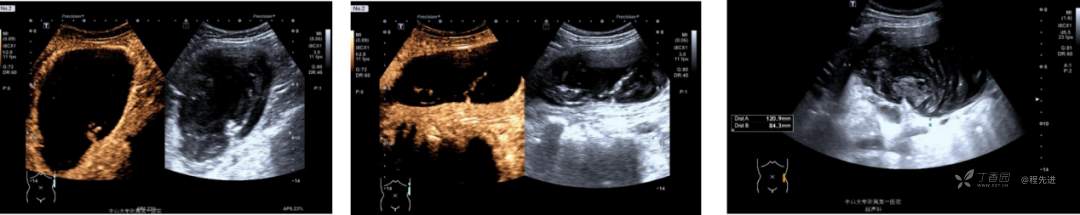

超声: